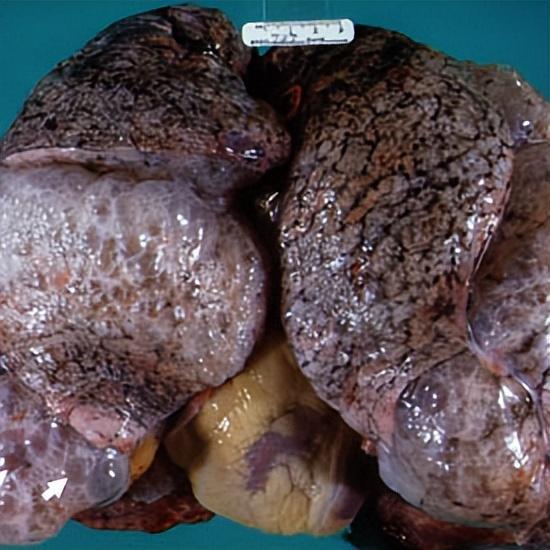

这是黑色的肺

这是慢阻肺

吸烟对肺功能的损伤极大。戒烟是一种及时止损的行为。

虽然戒烟后肺功能的恢复过程比较漫长,但依然可以提升生活质量,维持肺部长期健康。

图源:腾讯医典